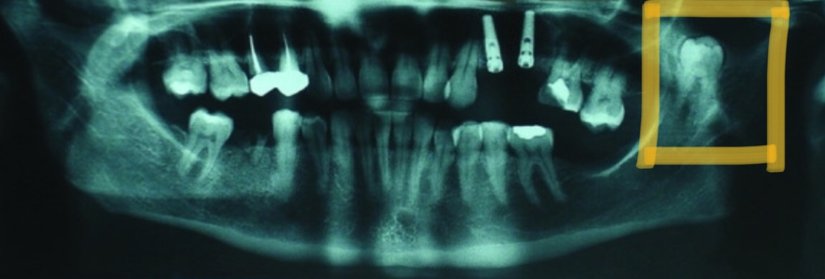

Yukarıda görülen vakada ise maxiller sinüste süren bir 20 yaş dişi görüyoruz. Sol üst 20 yaş dişi olması gereken yerde sürmek yerine, kafa boşluklarımızdan olan maxiller sinüste sürmeye karar vermiş olmalı. Sağ 20 yaş dişi doğru pozisyonunda sürerken, sol taraftaki diş hem yanlış yerde sürmüş hem de yine kendisi gibi oldukça kalsifiye bir yapıya eşlik etmekte.

Dişin morfolojisinin de normalden oldukça sapmış olduğunu izlediğimiz bu vakada hasta, yanağına yayılan yoğun ağrı ile uzun süre vakit geçirmiş ve ağrının başlamasından ancak 1 yıl sonra kaynağın bu diş olduğu anlaşılmıştır.

Yukarıdaki vakada fazla uzaklaşmamış bir 20 yaş dişi, hastada herhangi bir şikayete neden olmadığından bulunduğu yerde öylece bırakılmasına karar verilmiş.